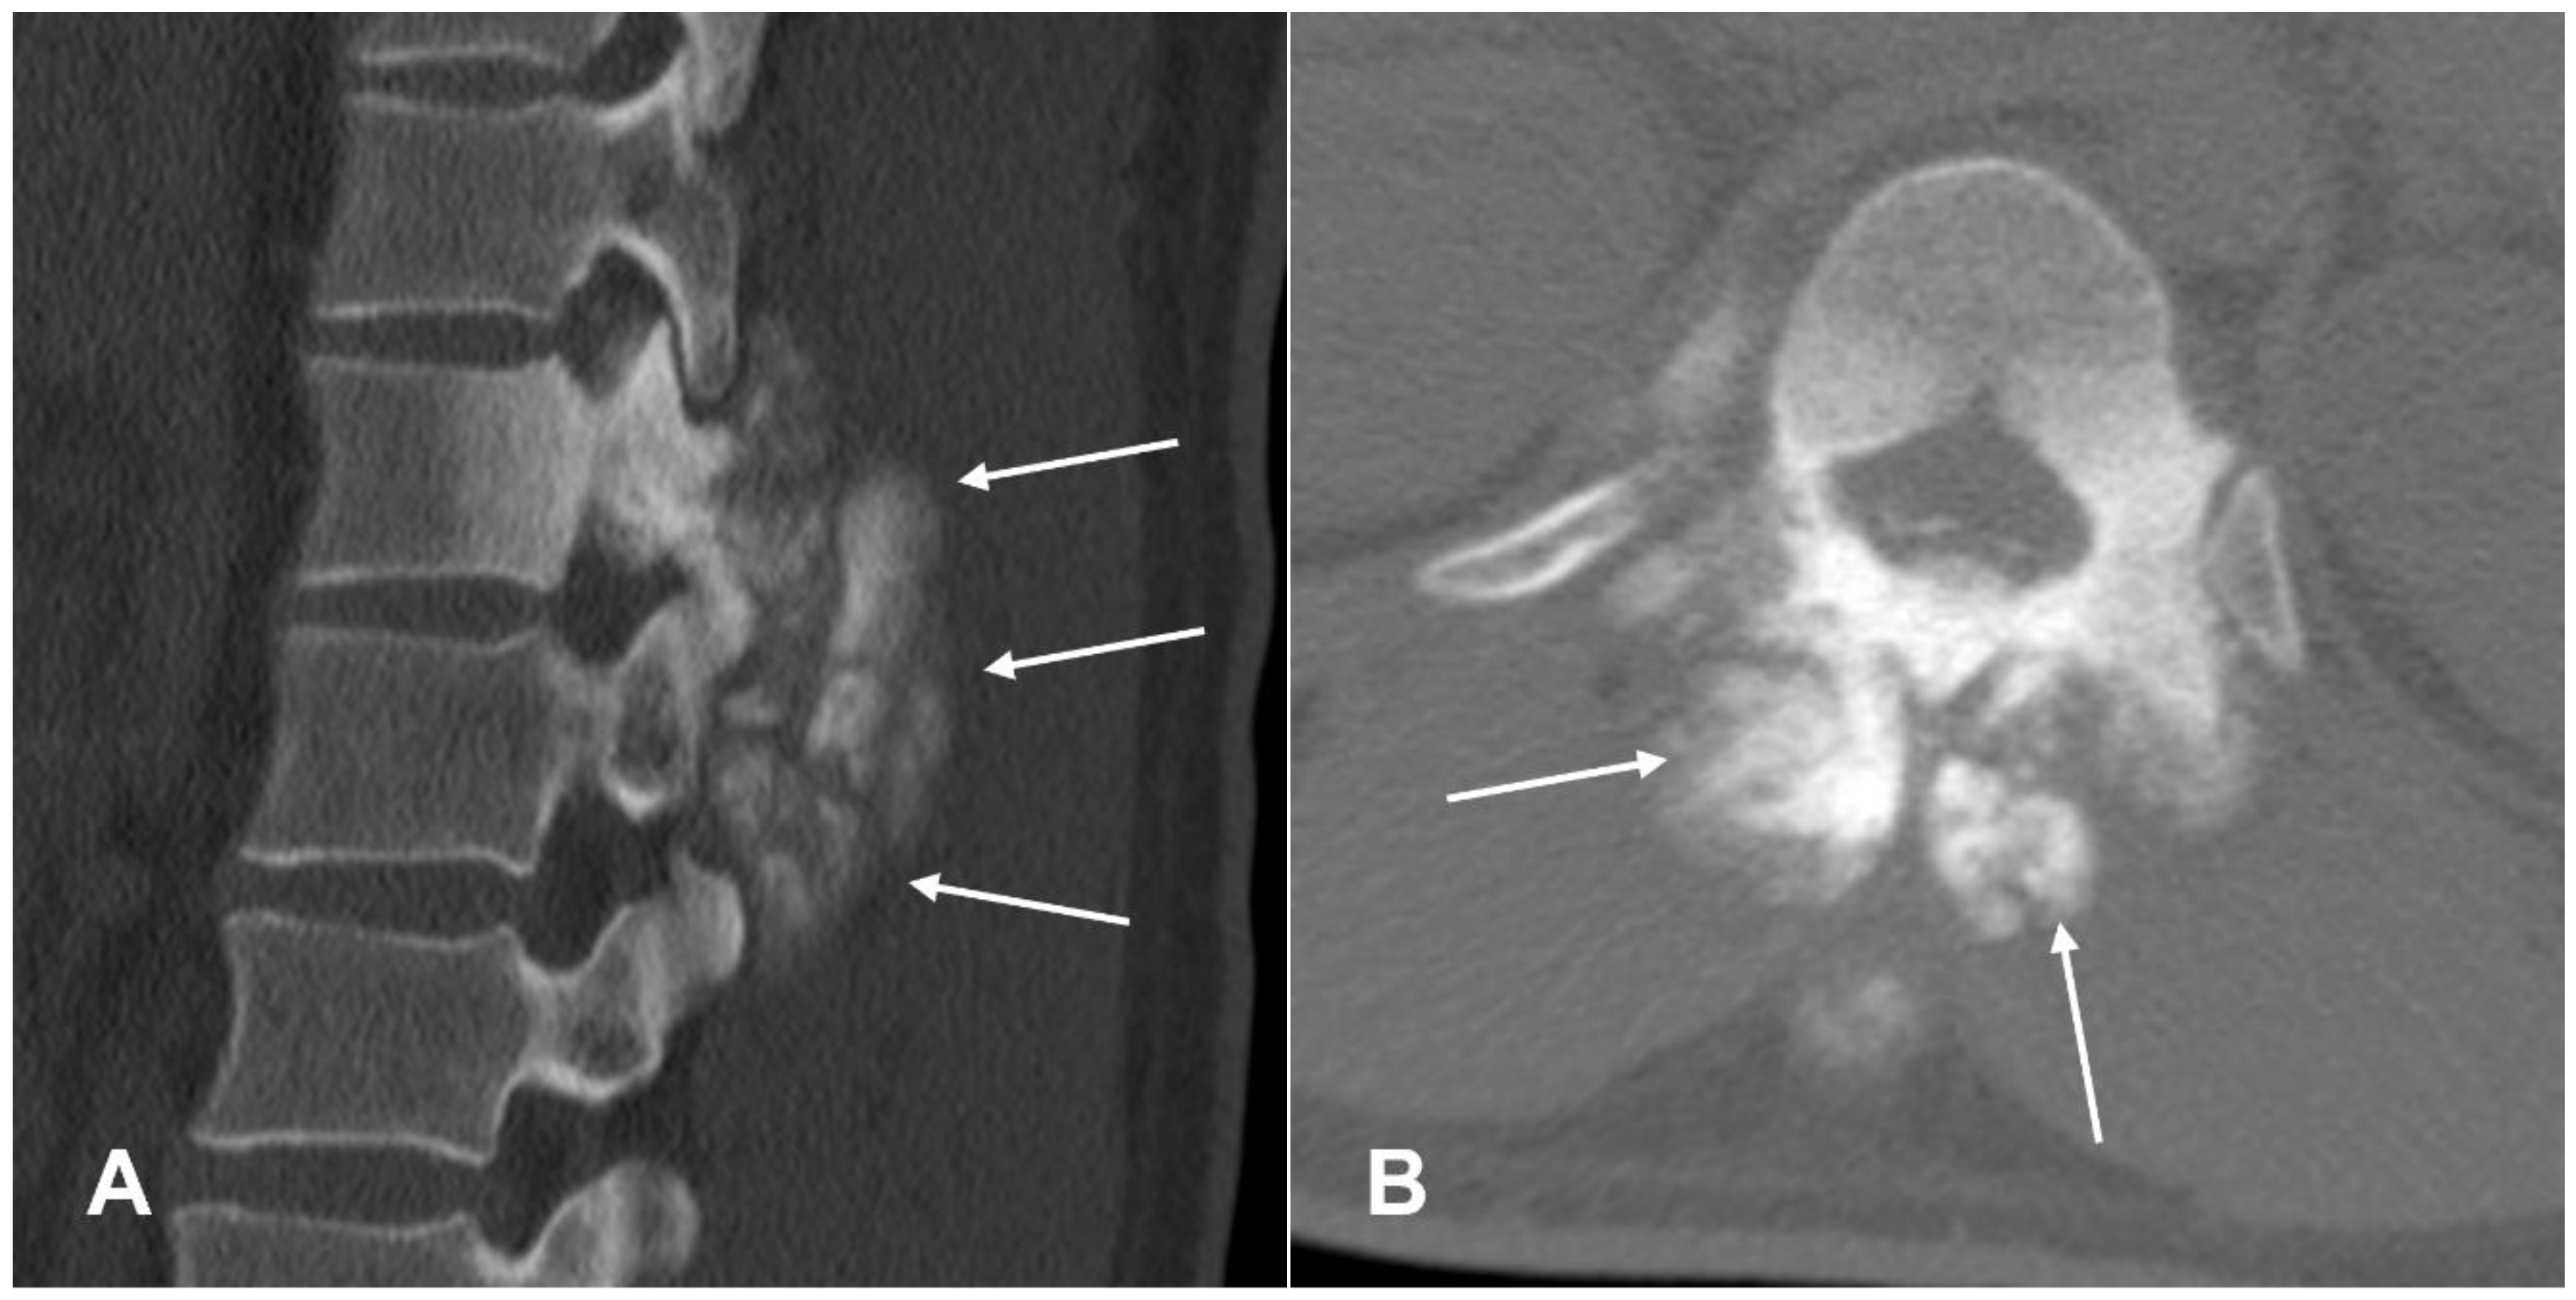

3.1.2. Secondary Osteosarcoma

- Meazza, C.; Giovanna, S.; Nigro, O.; Gattuso, G.; Francesco, B.; Podda, M.; Luksch, R.; Biassoni, V.; Schiavello, E.; Ferrari, A.; et al. Secondary Osteosarcoma: A Challenge Indeed. Int. J. Clin. Oncol. 2023, 28, 184–190. [Google Scholar] [CrossRef] [PubMed]

- Hansen, M.F.; Seton, M.; Merchant, A. Osteosarcoma in Paget’s Disease of Bone. J. Bone Miner. Res. 2006, 21, P58–P63. [Google Scholar] [CrossRef] [PubMed]

- Dray, M.S.; Miller, M.V. Paget’s Osteosarcoma and Post-Radiation Osteosarcoma: Secondary Osteosarcoma at Middlemore Hospital, New Zealand. Pathology 2008, 40, 604–610. [Google Scholar] [CrossRef] [PubMed]